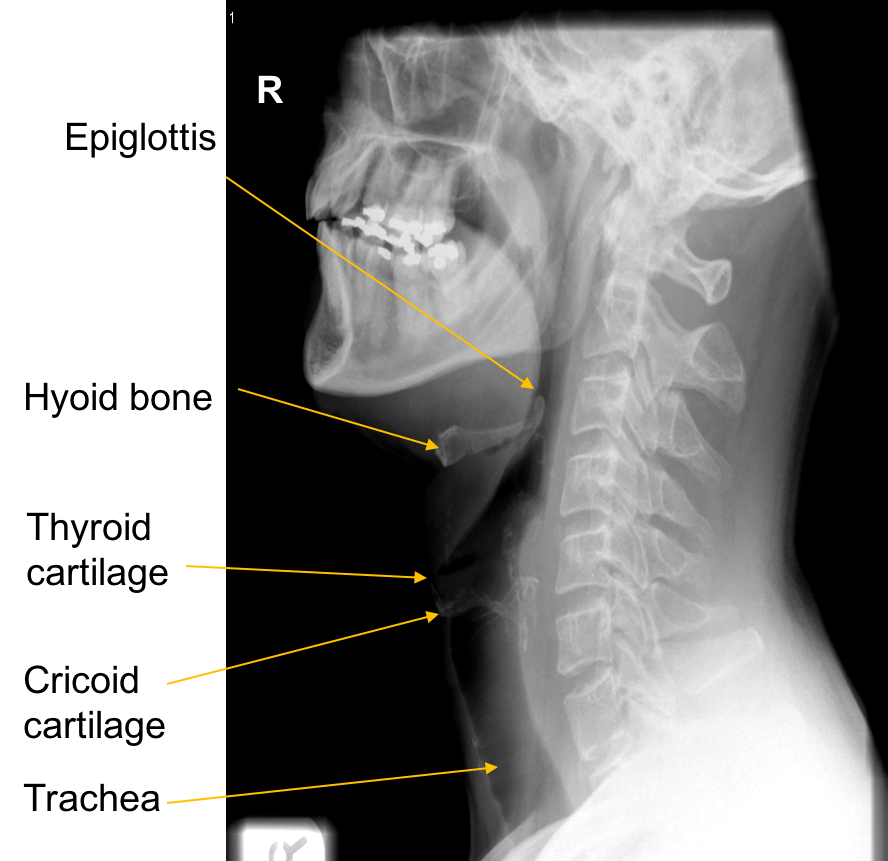

Soft tissue neck – check chicken bones etc.

Larynx – short passage connects laryngopharynx with trachea. Lies in the midline of neck anterior to fourth - sixth cervical vertebrae.

Wall of larynx composed of nine pieces of cartilage held together by membranes & muscle fibres. Three of the pieces of cartilage are single (thyroid, epiglottis, cricoid) three are paired (arytenoid , cuneiform, corniculate)

Arytenoid most important as influence positions and tensions of vocal cords.